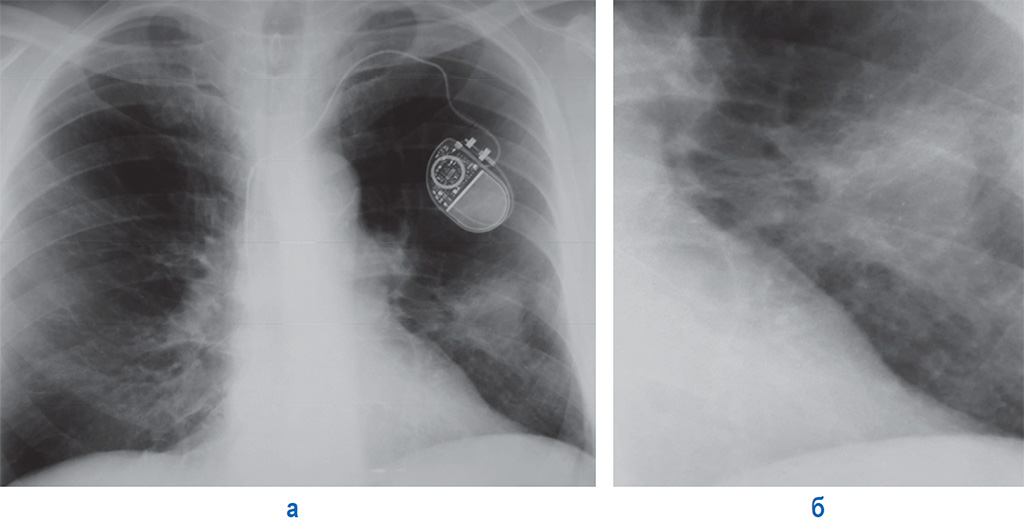

Рентгеновские снимки опухоли Панкоста